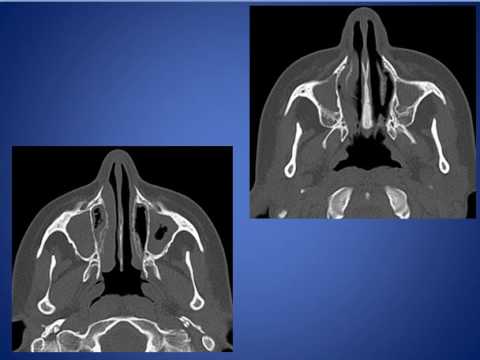

Синдром картагенера у детей

Синдром картагенера у детей 113 фотографий